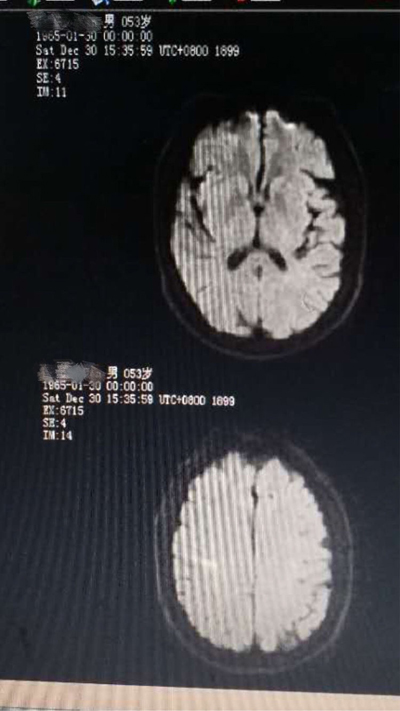

病例三:第二例脑梗死行阿替普酶溶栓治疗

患者彭某某,女,74岁,新市镇新书村人,因突起言语不清伴意识障碍2小时,于2018年2月3日入院,有高血压、冠心病史且姐妹有中风病史,留有后遗症。体查:嗜睡,言语含糊,体查欠配合,口角不斜,伸舌不能,四肢肌力3级,左侧巴氏症可疑,右侧正常,考虑急性脑梗死可能性大。

溶栓前头颅CT,排除脑出血

患者无静脉溶栓禁忌症,告知家属患者病情危重,溶栓风险大,可能效果欠佳,家属积极配合同意溶栓,立即启动阿替普酶静脉溶栓,约一天半左右神志转清,语言清晰,肢体肌力正常。

第二天复查头颅核磁未见明显异常